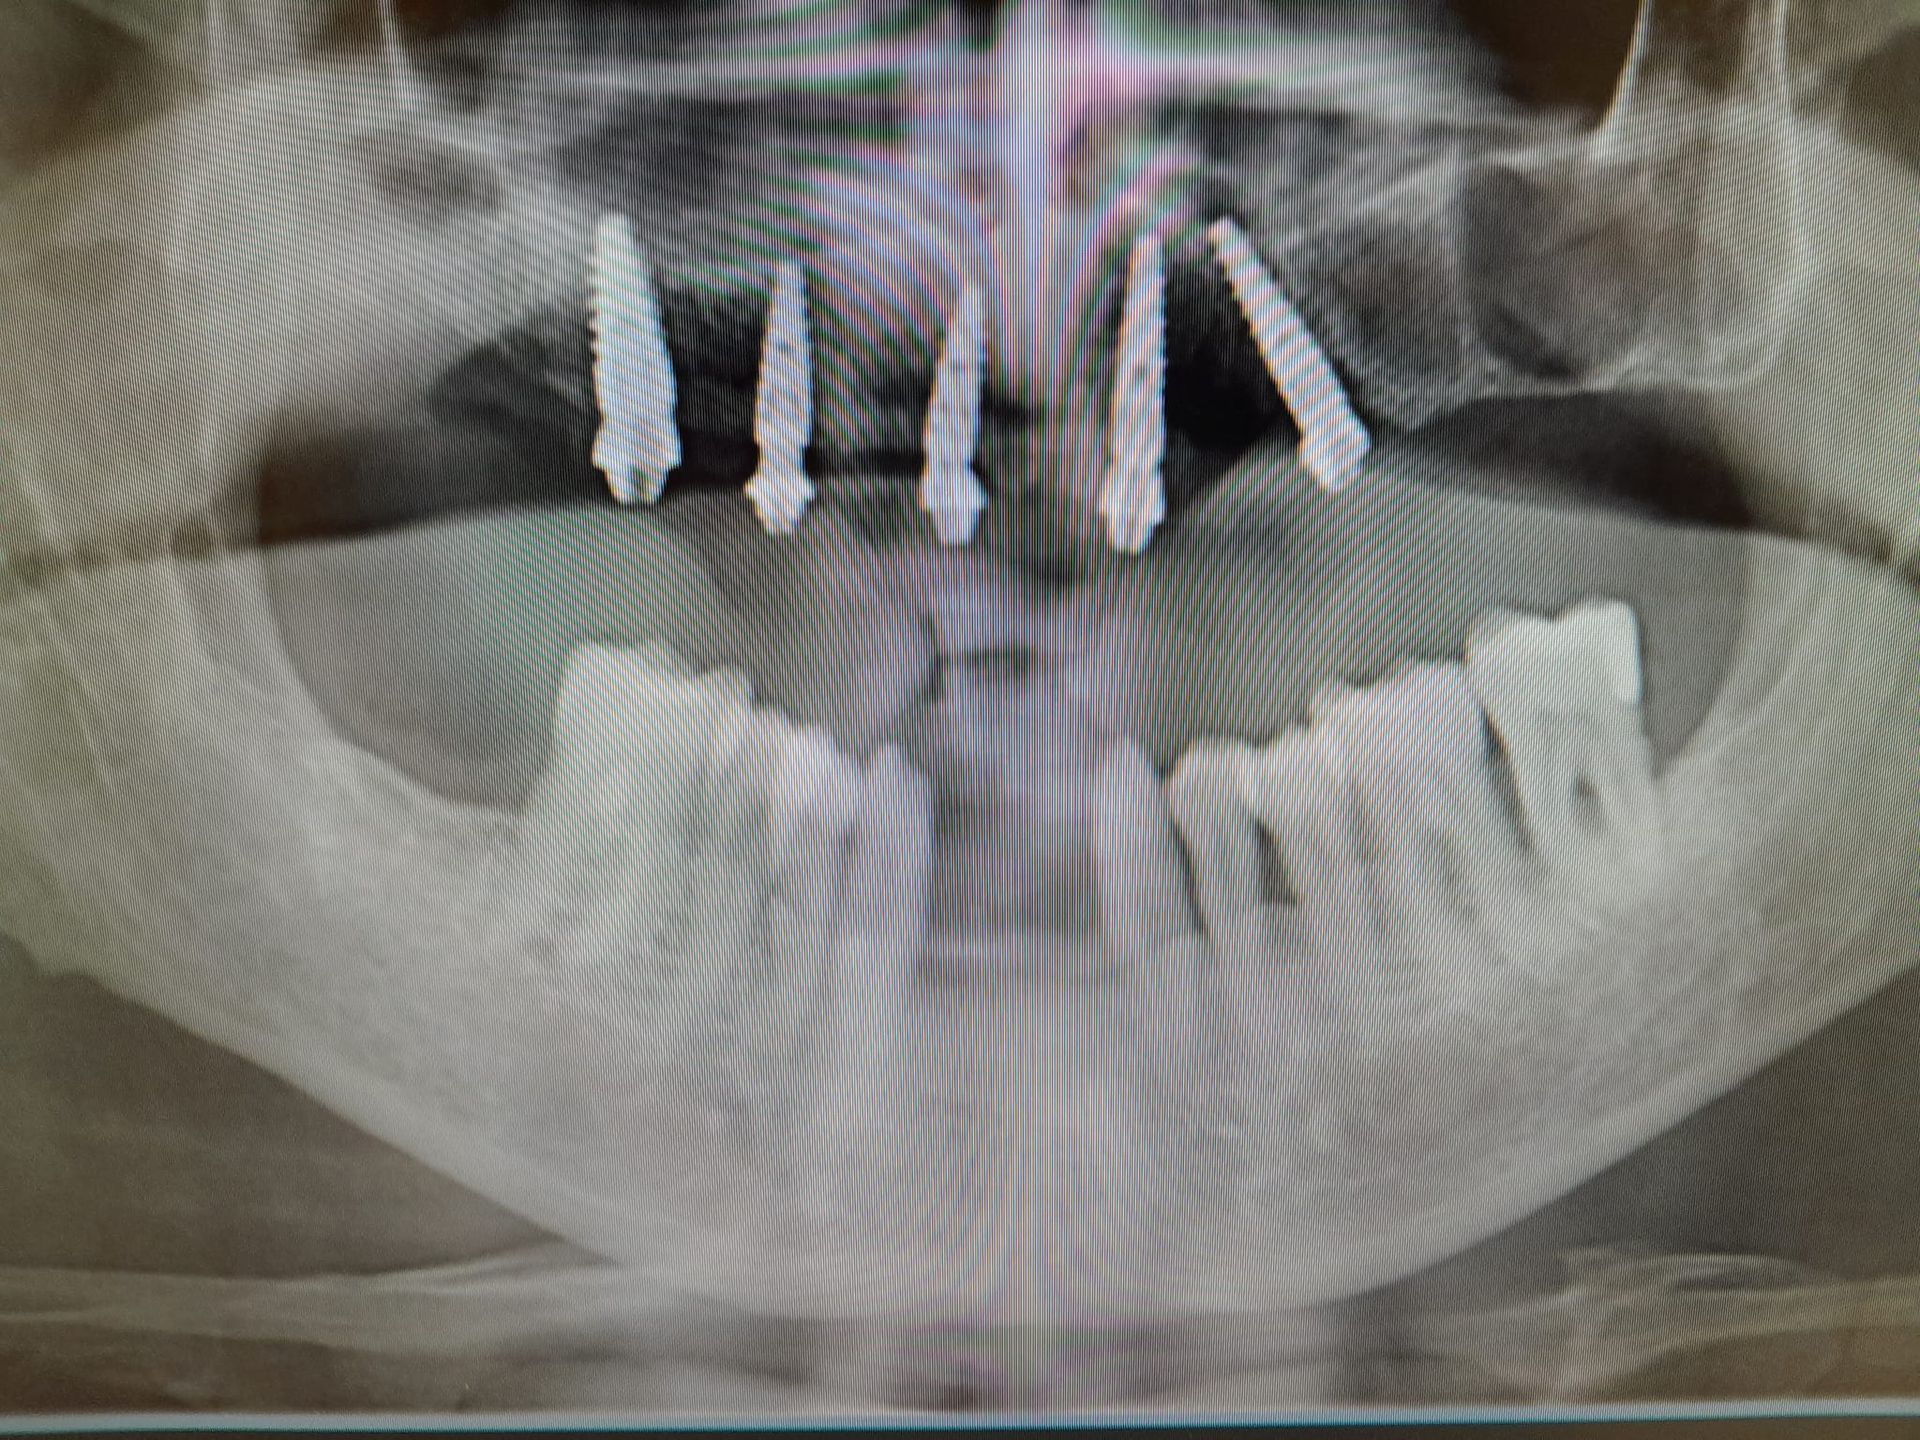

L’implantologia dentale è una branca dell’odontoiatria che ha l’obiettivo di ripristinare i denti mancanti mediante l’inserimento di radici artificiali in titanio (impianti dentali).

Le tecniche di implantologia dentaria permettono una riabilitazione permanente della masticazione